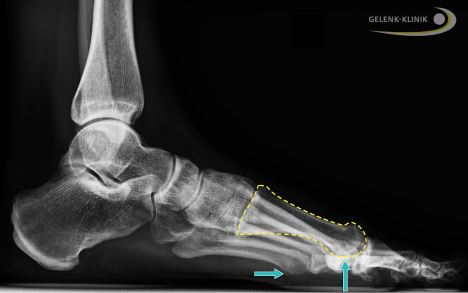

Es ist wichtig, Röntgenbilder unter Gewichtsbelastung des Fußes in verschiedenen Ebenen zu machen. Im Röntgenbild in mehreren Ebenen kann eine eigentlich für jede Art von Arthrose typische Veränderung des Knochens festgestellt werden:

- Einengung des Gelenkspaltes

- abgeflachte Form des Mittelfußkopfes

- Darstellung von Knochenspornen (Osteophyten) in der Umgebung des Gelenkspaltes

- Darstellung von subchondralen Zysten (Flüssigkeitseinschlüssen in Hohlräumen im Knochen)

Bei der Interpretation von Röntgenbildern ist Vorsicht geboten: Die Osteophyten können den Knorpelverlust im Gelenkspalt optisch ausgeprägter erscheinen lassen, als es der Wirklichkeit entspricht. Dabei beginnt die Arthrose meist dorsal, also im oberen Bereich des Gelenks. Der untere Bereich der Gelenkfläche des Großzehengrundgelenks ist deutlich weniger stark beeinträchtigt.